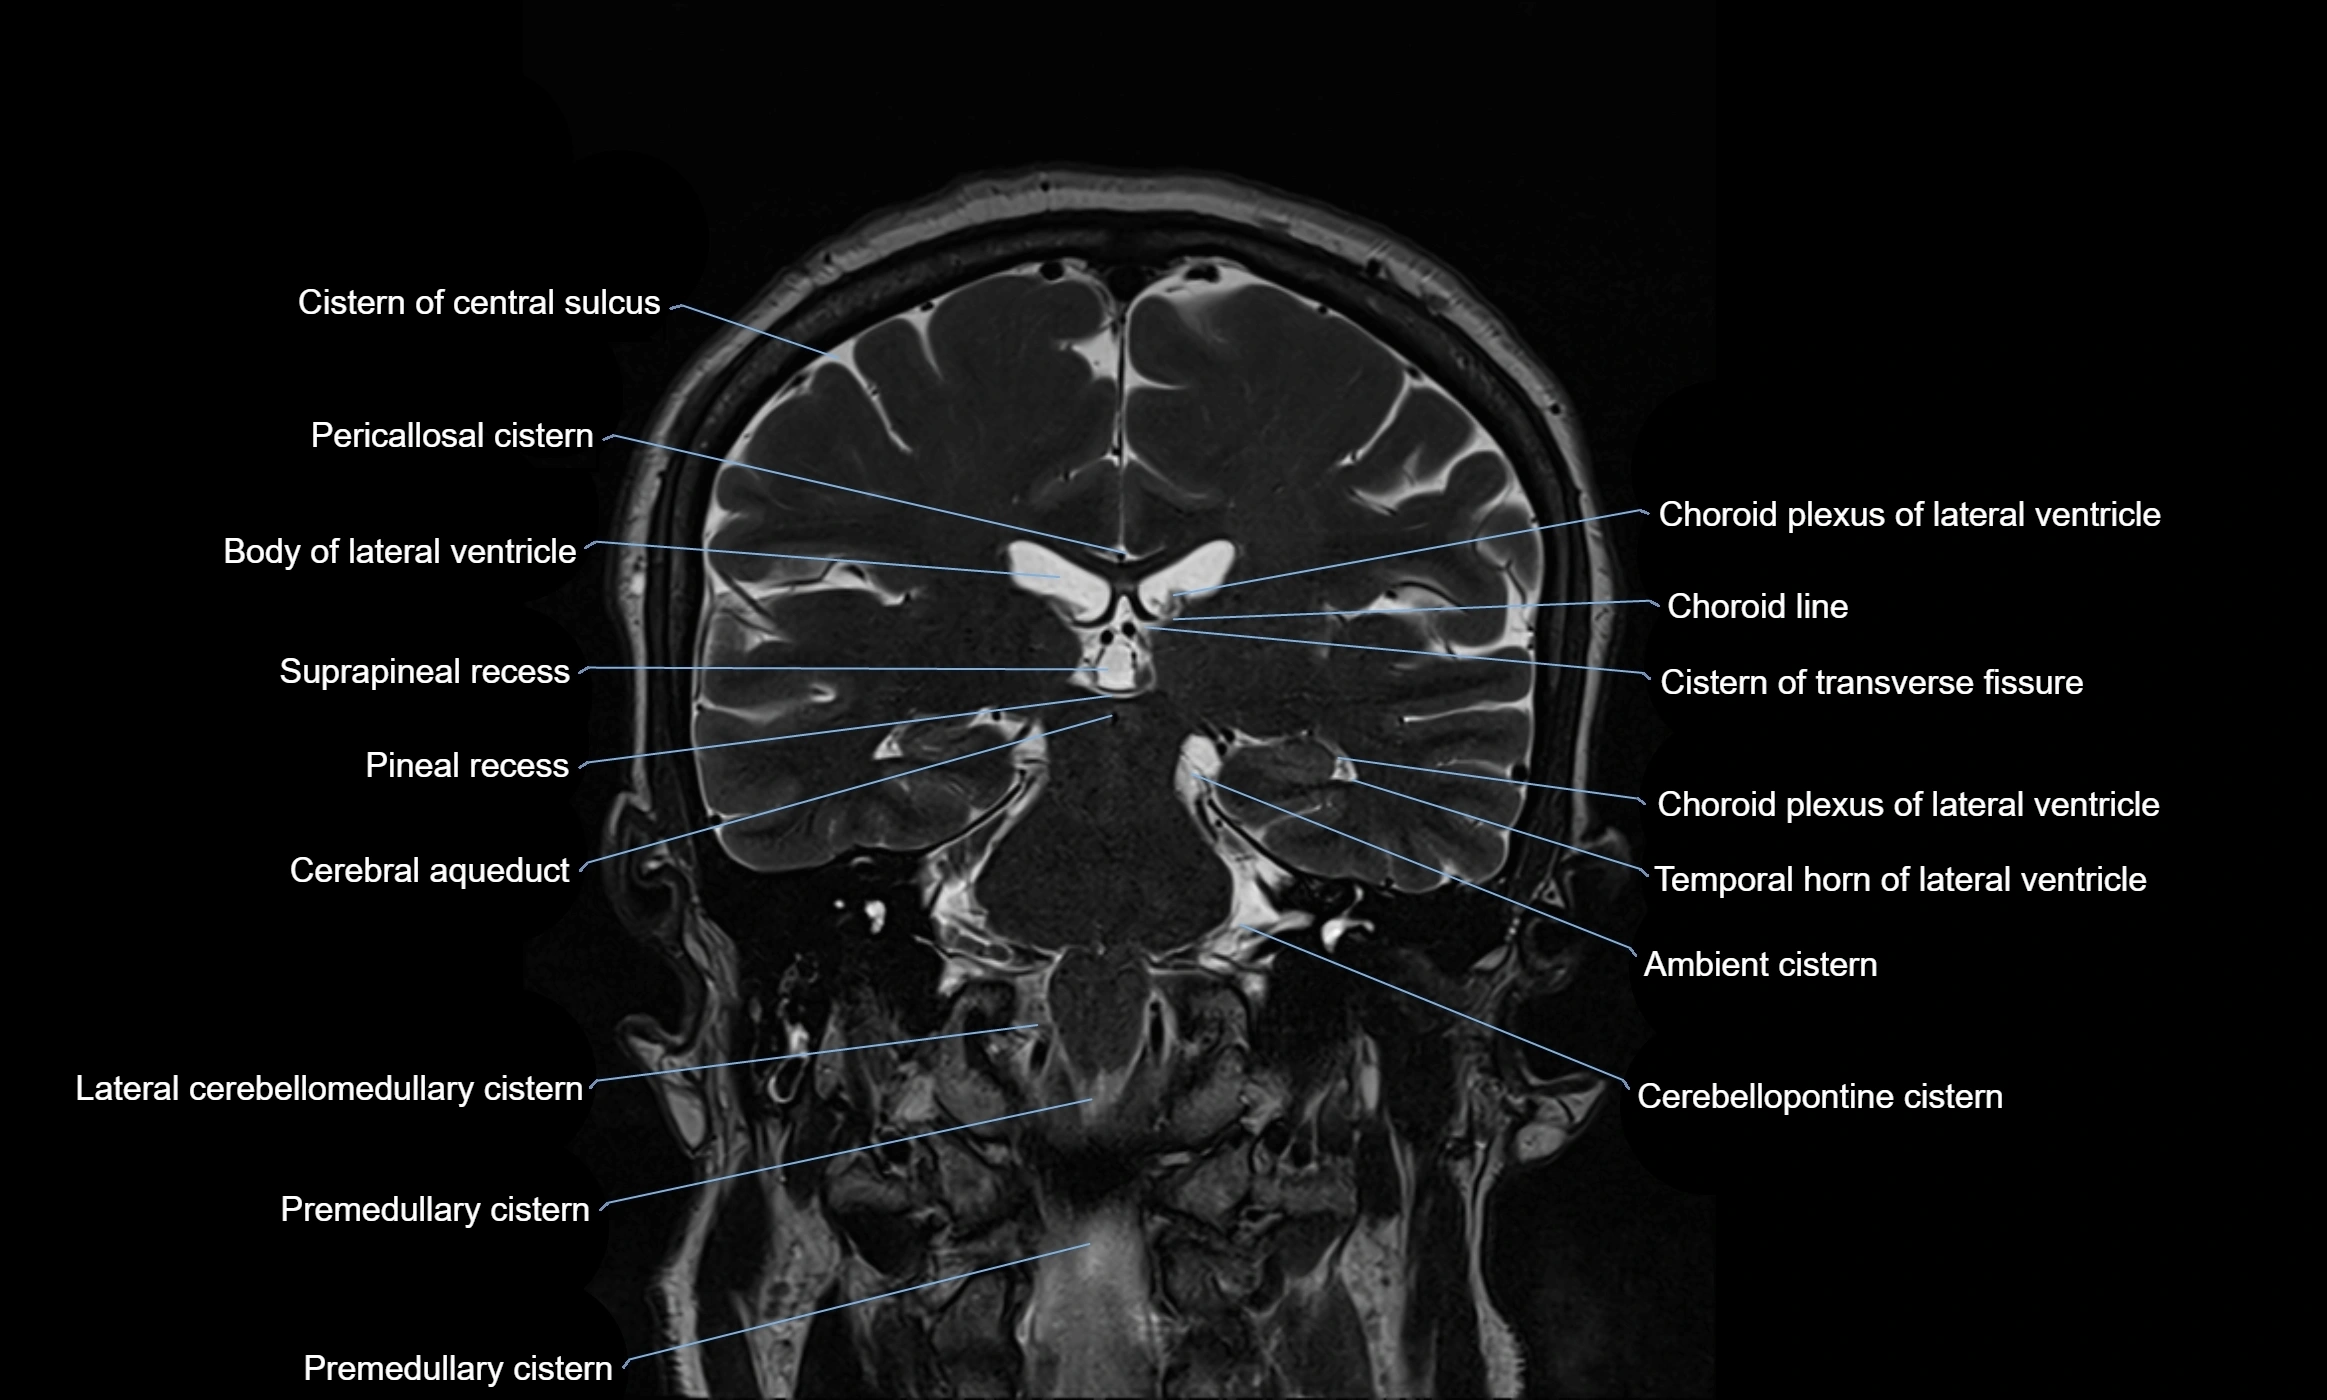

MRI images

image